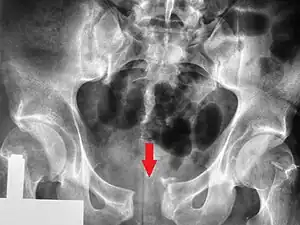

This abnormally wide gap can be diagnosed by radiologic studies such as X-ray, Ultrasound, MRI, CT scan or bone scan. While X-Ray is the gold standard to identify a separation of the pubic symphysis, a decision must be made in regard to which imaging modality to utilize that is patient and case-specific.[3]

X-ray

An X-ray film obtained in the AP view of the pelvic inlet and outlet will show a marked gap between the pubic bones.[3] A normal pelvis will show a gap that is 4–5 mm. However, in pregnancy the hormonal influences cause relaxation of the connecting ligaments and the bones separate up to 9 mm. A gap measuring greater than 10 mm indicates a pathological process.[3]